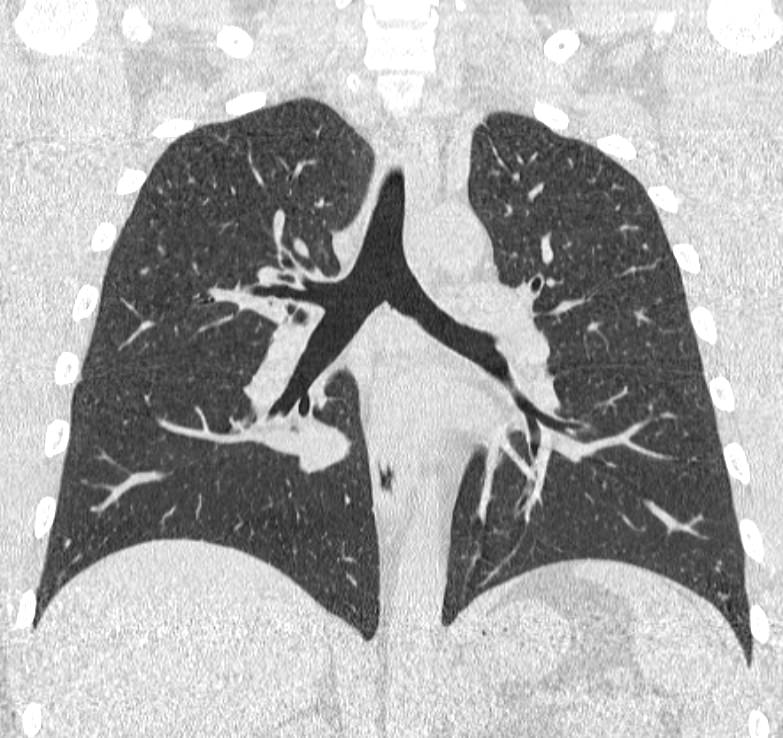

Компьютерная томография бронхов представляет собой виртуальную бронхоскопию, которая позволяет получить точную и достоверную информацию о состоянии трахеи, бронхов, а также оценить структуру легочной ткани, кровеносных сосудов, органов средостения. При обычной бронхоскопии эндоскопический зонд вводится внутрь через дыхательные пути и производится осмотр слизистой трахеи и бронхов, поэтому процедура относится к инвазивным и часто проводится под наркозом.

На основе данных, полученных при сканировании, аппарат создает наглядную 3D модель бронхиального дерева с высочайшей точностью и достоверностью, которая позволяет просматривать интересующие анатомические структуры в разных плоскостях. Метод обладает высокой точностью и дает возможность исследовать мелкие бронхи и бронхиолы, которые из-за узкого просвета бывает невозможно осмотреть при помощи эндоскопической бронхоскопии (возможности метода ограничены размером зонда).

С помощью виртуальной бронхоскопии можно выявить объемные образования в трахее, бронхах, определить степень сужения просвета дыхательных путей. Кроме того, компьютерная томография позволяет оценить состояние окружающих тканей, выявить прорастание опухоли в близлежащие органы, обнаружить метастазирование в регионарные лимфоузлы и ткань легкого.

КТ бронхов помогает диагностировать воспалительные заболевания бронхов и легких, бронхоэктатическую болезнь, инфекционные заболевания, травматические повреждения грудной клетки, аномалии развития.